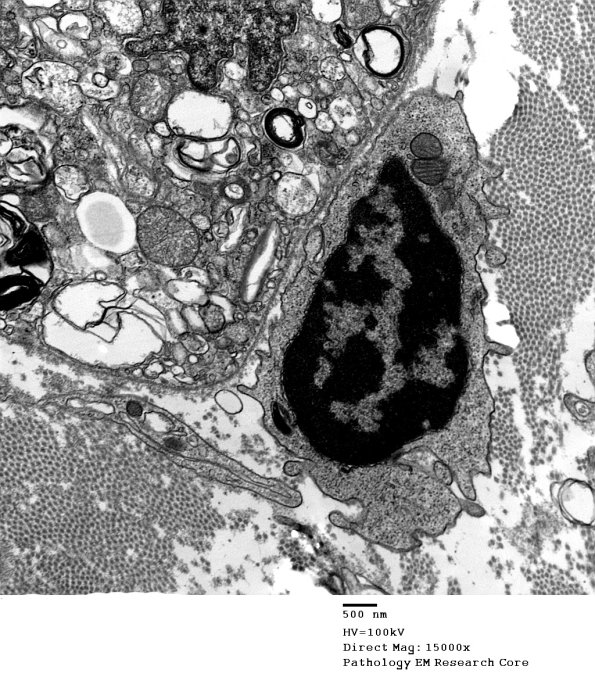

Early contact of macrophage processes with a debris laden Schwann cell.